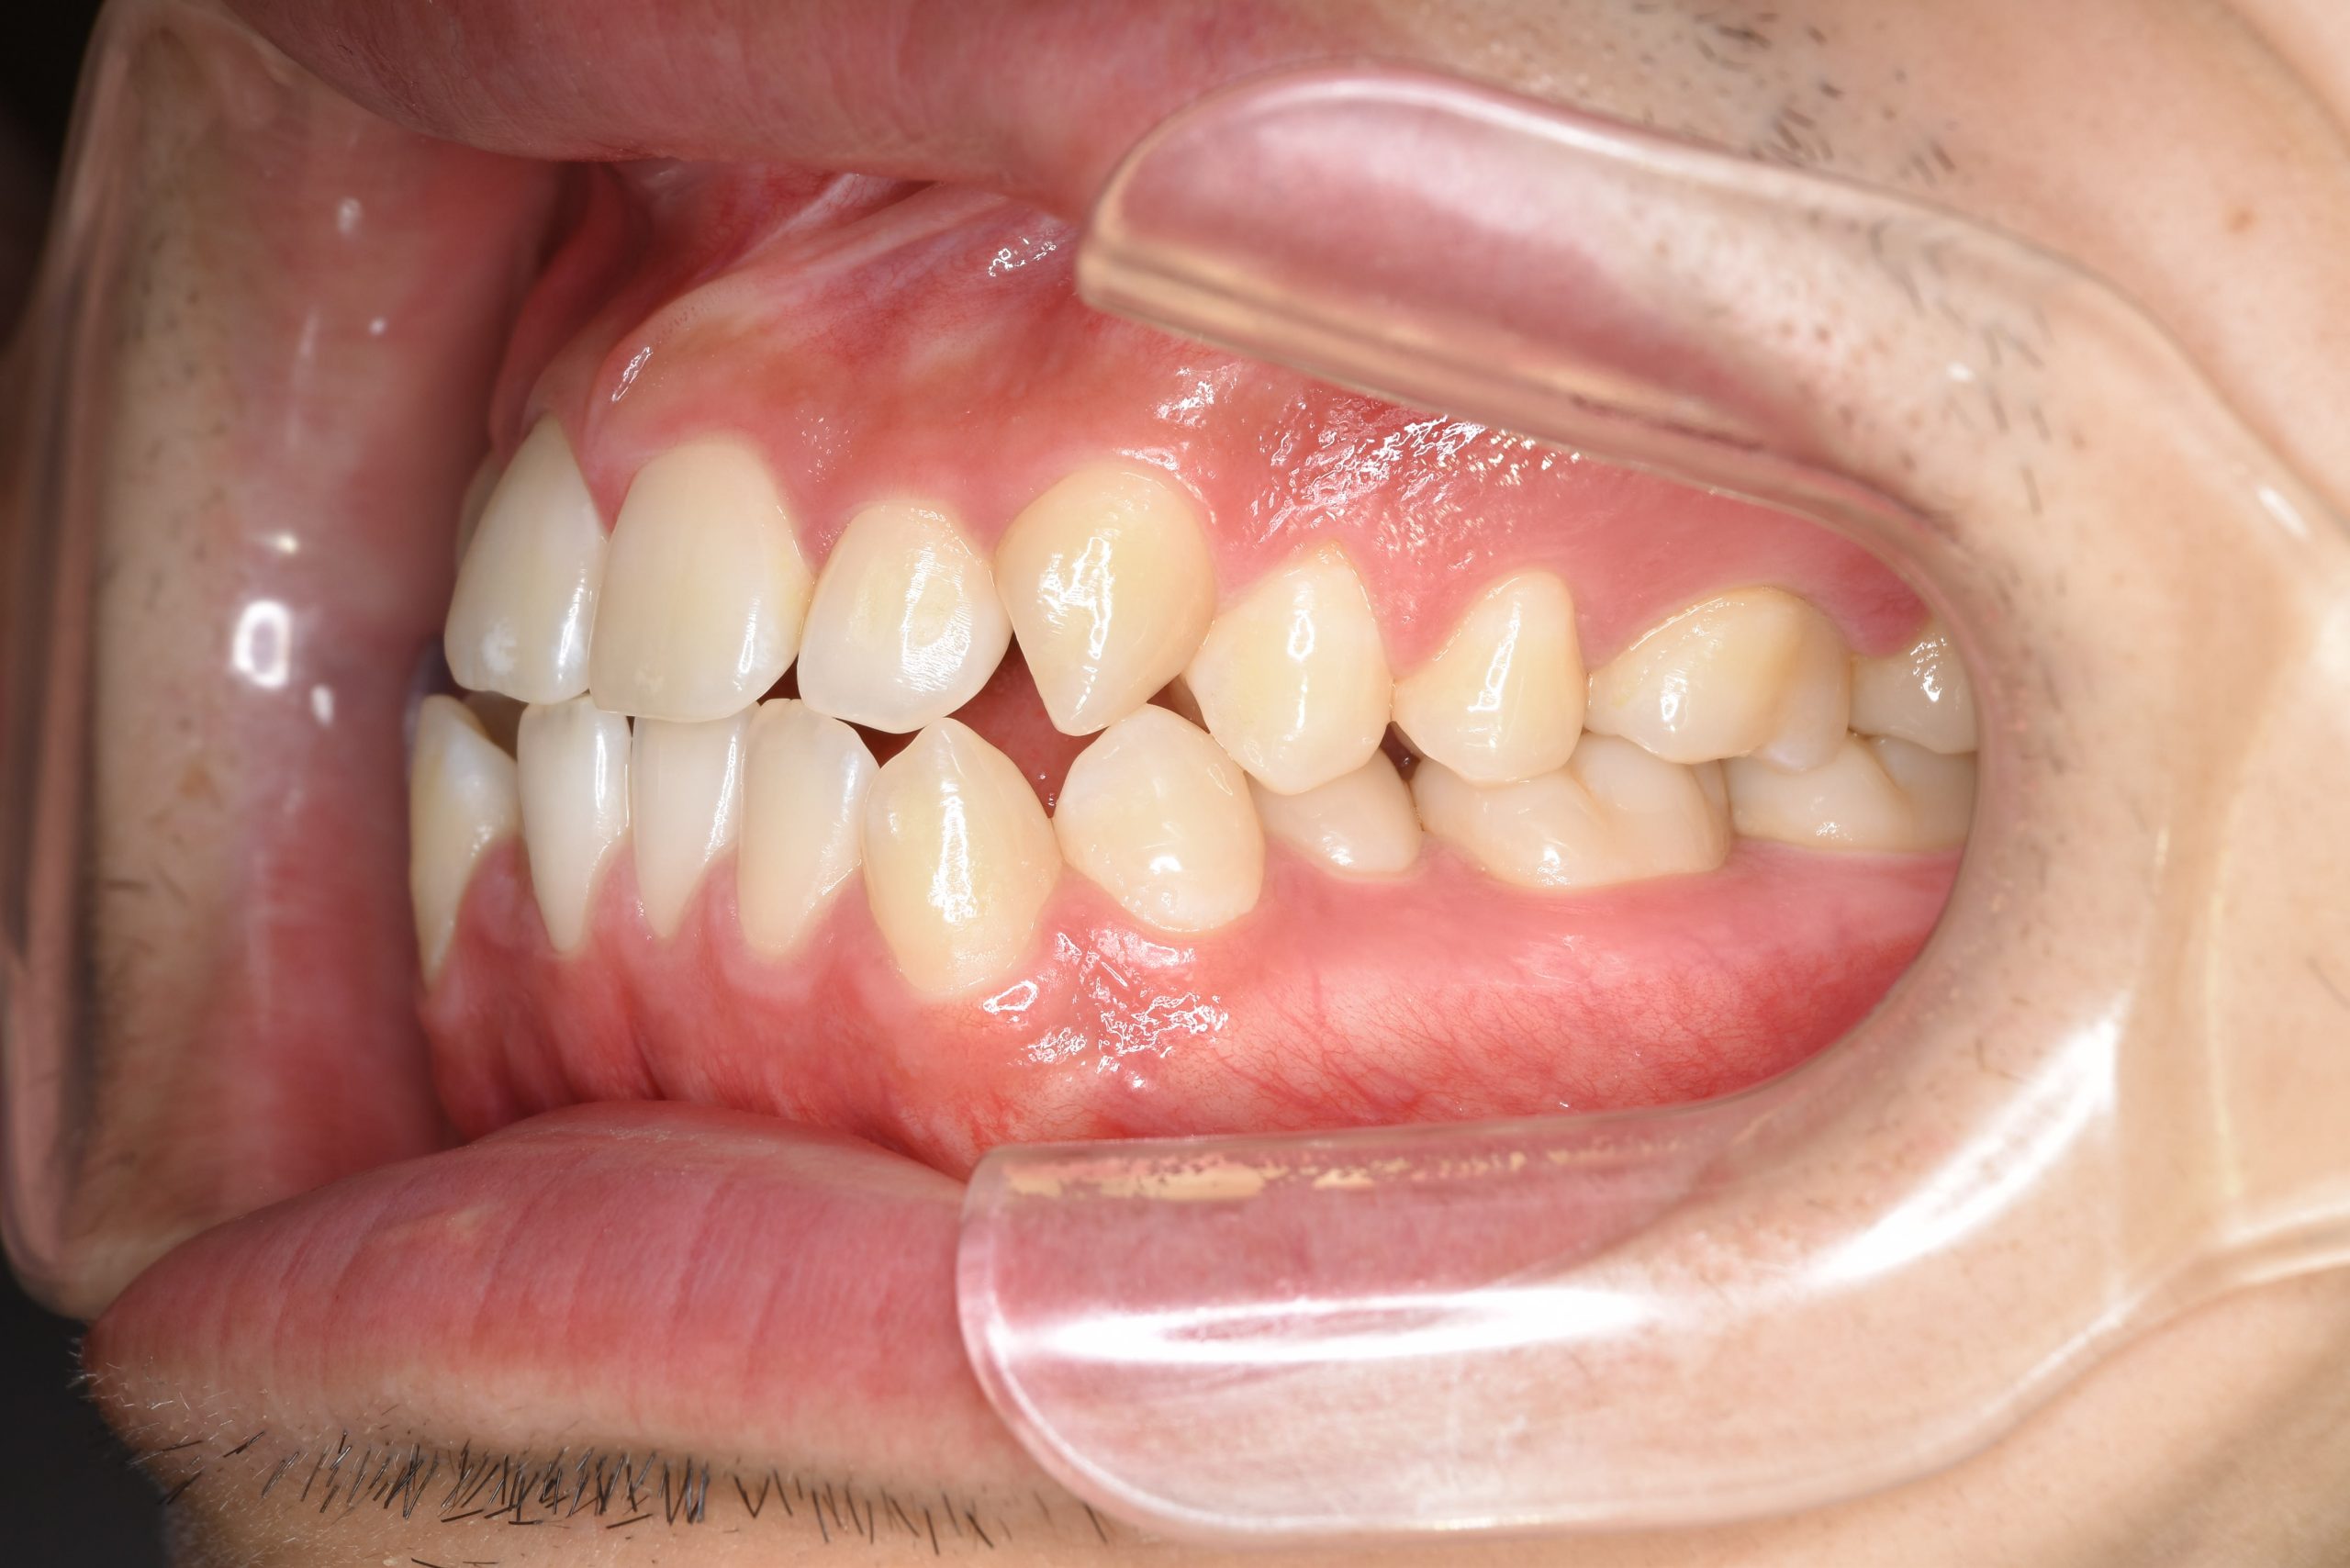

ビフォー

ワイヤー矯正治療|症例_495

主訴 受け口|かみ合わせ|面長

施術内容 MSEと下顎リンガルアーチを用いて上下顎骨を拡大した。

その後マルチブラケット装置とミニインプラントを用いて

非抜歯で歯牙を配列し、良好な咬合を獲得した。

下口唇の突出感と鼻閉症状は改善した。

治癒期間 2年1か月間